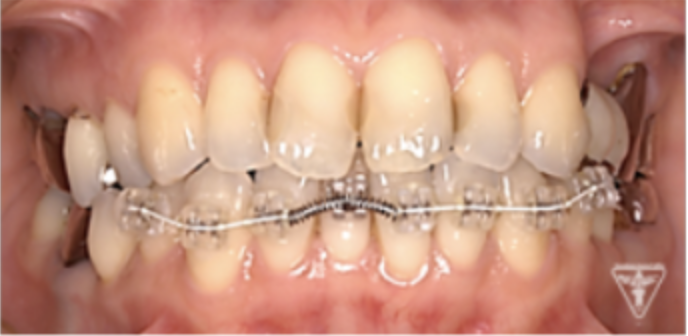

矯正治療

矯正治療による歯軸、叢生改善